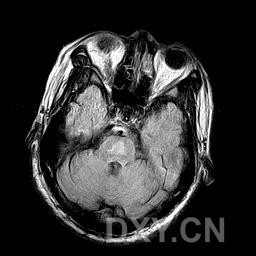

腦部病理改變與病因及病程長短有關。最重要特徵是AlzheimerⅡ型星形膠質細胞廣泛存在於大腦皮質基底核、黑質、紅核小腦齒狀核及橋核等部位程度與神經症狀嚴重程度及病程長短呈正比。慢性病例可見皮質瀰漫性片狀假分層樣壞死皮質與髓質交界處呈腔隙狀態神經細胞及髓鞘變性,部分細胞核內可見包涵體。屍檢腦部有斑片狀皮層壞死或假層狀壞死,皮質髓質連線處、紋狀體和小腦白質內有微小空腔形成。鏡下可見原漿型星形細胞數量和體積均增加。大腦皮層、小腦、齒狀核和豆狀核的神經細胞以及有髓纖維發生變性,星形膠質細胞出現含糖原的核內包含體。

2.腦部CT、MRI掃描有助鑑別診斷。